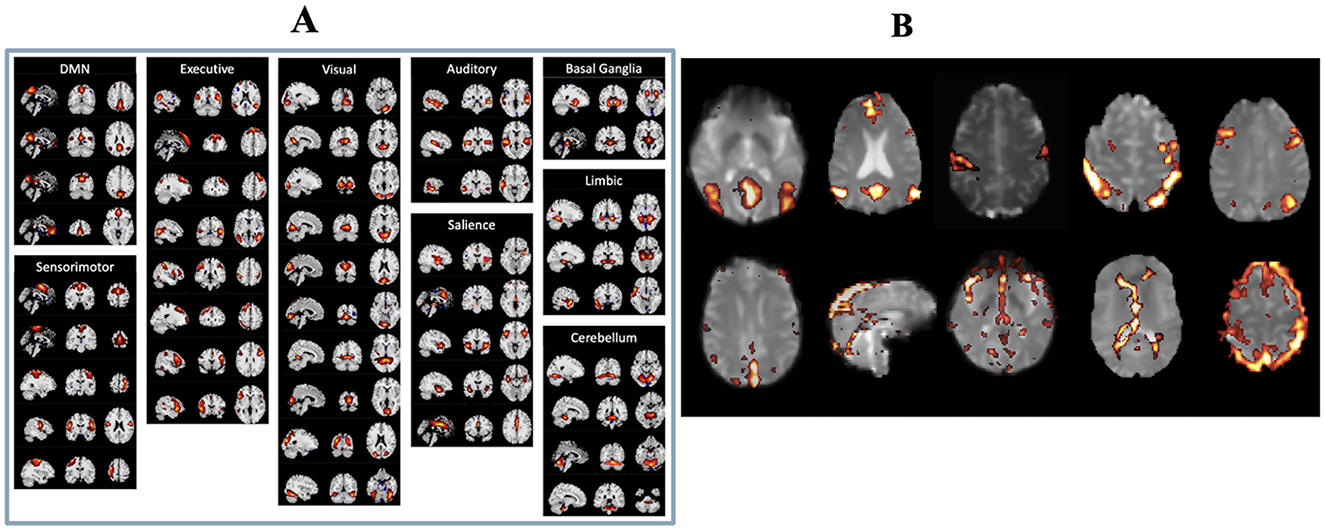

After ICA, two authors (CMM and MA) manually inspected the ICs, following the selection guide outlined by Boerwinkle et al. (21) to distinguish meaningful components from noise components. Both authors were blinded to both the patients' surgical outcomes and LITT laterality at the time of component selection to minimize potential bias. Components were classified based on combined evaluation of spatial maps, temporal dynamics, and frequency spectra, with reference to canonical resting-state network templates. Components showing edge artifacts, head motion, high-frequency noise (>0.1 Hz), or physiologic/vascular signal contamination were excluded. ICs were deemed meaningful if they exhibited peak FC patterns in known resting state networks (RSNs), gray matter, or the brainstem, had power spectra predominantly in the low-frequency range, and showed time courses characterized by slow, regular oscillations. Representative examples of both included and excluded ICs are shown in Figure 1. To minimize any potential ambiguity related to the arbitrary sign of ICA-derived z-scores, we applied a positive threshold of z > 2.5 to identify meaningful components. Only components with positively weighted voxels exceeding this threshold were retained. We did not observe any meaningful resting-state networks with significant negative z-scores (z < −2.5), ensuring that all selected components reflected positive connectivity patterns relative to the global mean.

Figure 1. (A) List of real resting state functional networks. (B) Examples of independent components considered to be real (top row) and independent components considered to be artifactual (bottom row).

Functional MRI images display brain regions associated with various networks and activities. Panel A shows different brain networks, including DMN, Executive, Visual, Auditory, Sensorimotor, Basal Ganglia, Limbic, Cerebellum, and Salience, with highlighted areas. Panel B highlights other brain regions, with vibrant areas indicating activity or connectivity differences.